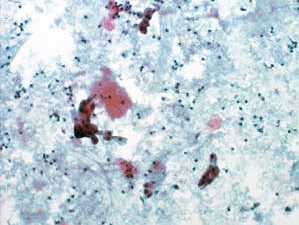

图7-10 不满意样本(中倍、液基、巴氏染色)

背景血性污浊,细胞散在,细胞量过少。